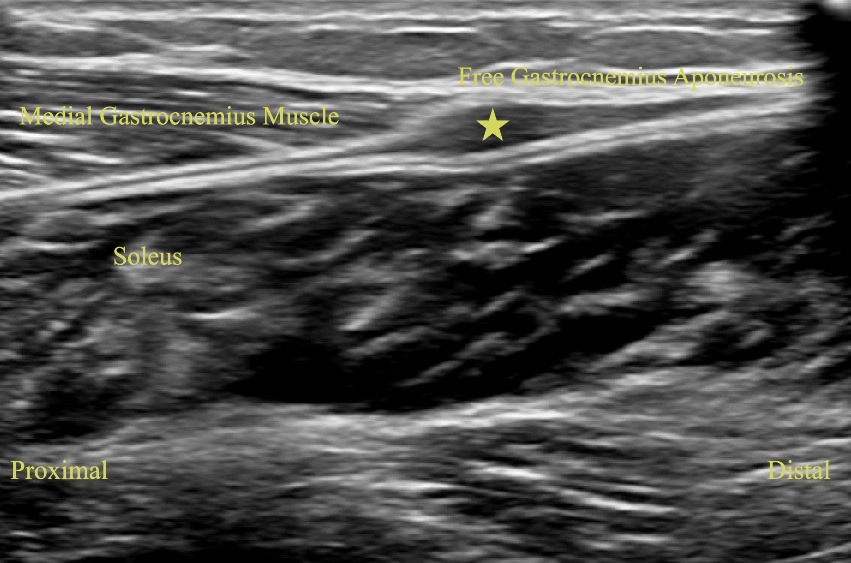

Long Axis view of Left Medial Gastrocnemius Soleus Aponeurosis with Free Gastrocnemius Aponeurosis Hematoma (Star)

Long axis view of Left Medial Gastrocnemius and Soleus Aponeurosis with Free Gastrocnemius Aponeurosis Hematoma